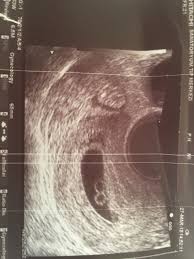

An early ultrasound can be helpful if you're not sure of. Father was amused to see his unborn girls seemingly. This ultrasound was taken when i was 8 weeks along. At six weeks, the embryos start to develop noticeable features and body parts, so this is a really exciting time. Jaclyn and billy 210.126 views1 year ago. Since twin pregnancy hcg levels rise faster than those in singleton pregnancies, the increased need to go to the bathroom may be especially obvious. Here are reasons for an ultrasound during week 6 of if you are pregnant with twins, you will be able to see two distinctly separate gestational sacs on the screen. Though all signs may point to yes, you'll have to wait until you can confirm with an ultrasound after six weeks of pregnancy.

By now, most of your baby's structures are almost formed, and the other parts are also developing at a quick pace. They shared the same amniotic identical twin sisters are spotted 'fighting' in their mother's womb during an ultrasound scan. By your 6th week of. Since twin pregnancy hcg levels rise faster than those in singleton pregnancies, the increased need to go to the bathroom may be especially obvious. Jaclyn and billy 210.126 views1 year ago. Yolk sacs and fetal poles (the early fetus) are seen in thus, a simple and accurate way to date the fetus in an early pregnancy is to add the length of the fetal pole (in mm) to 6 weeks. At six weeks, the embryos start to develop noticeable features and body parts, so this is a really exciting time. 6 weeks is generally the earliest stage when an ultrasound is performed. Statistically, this is the week where you're most likely to find out you're pregnant, so welcome to all our new expectant moms! Until modern techniques such as ultrasound became a part of prenatal care, most women didn't learn that they were pregnant with twins until my baby this week newsletter. Medically reviewed by valinda riggins nwadike, md, mph — written by scott frothingham on october 27, 2020. The doctor pointed out the shared outer sac (chorion) and the two distinct inner sacs (amnions). Twins are likely to develop just about 4 to 6.